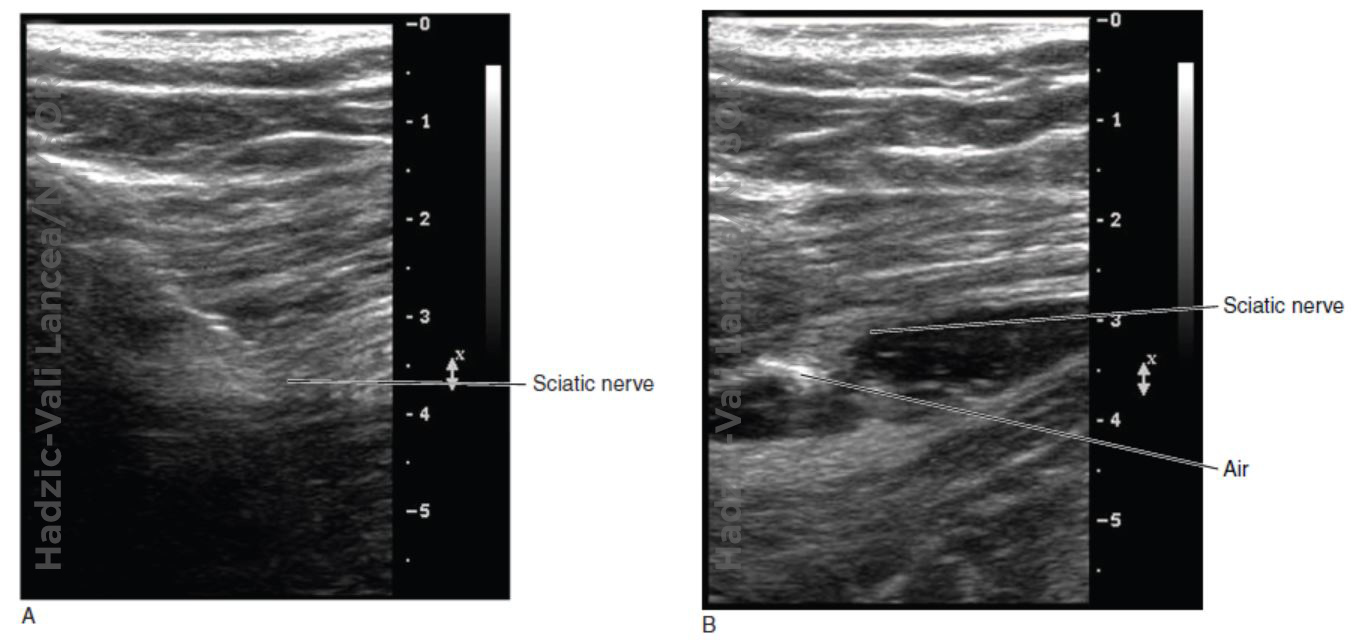

Optimizing an Ultrasound Image NYSORA The New York School of Regional How To Optimize Ultrasound Images optimizing an ultrasound image can be challenging, especially for the new practitioner. by simply testing a few controls, you can quickly gain a basic understanding of ultrasounds and become a master at image optimization. in order to obtain optimal ultrasound images, it is necessary to adjust several parameters continuously during the examination. from a medical as. How To Optimize Ultrasound Images.